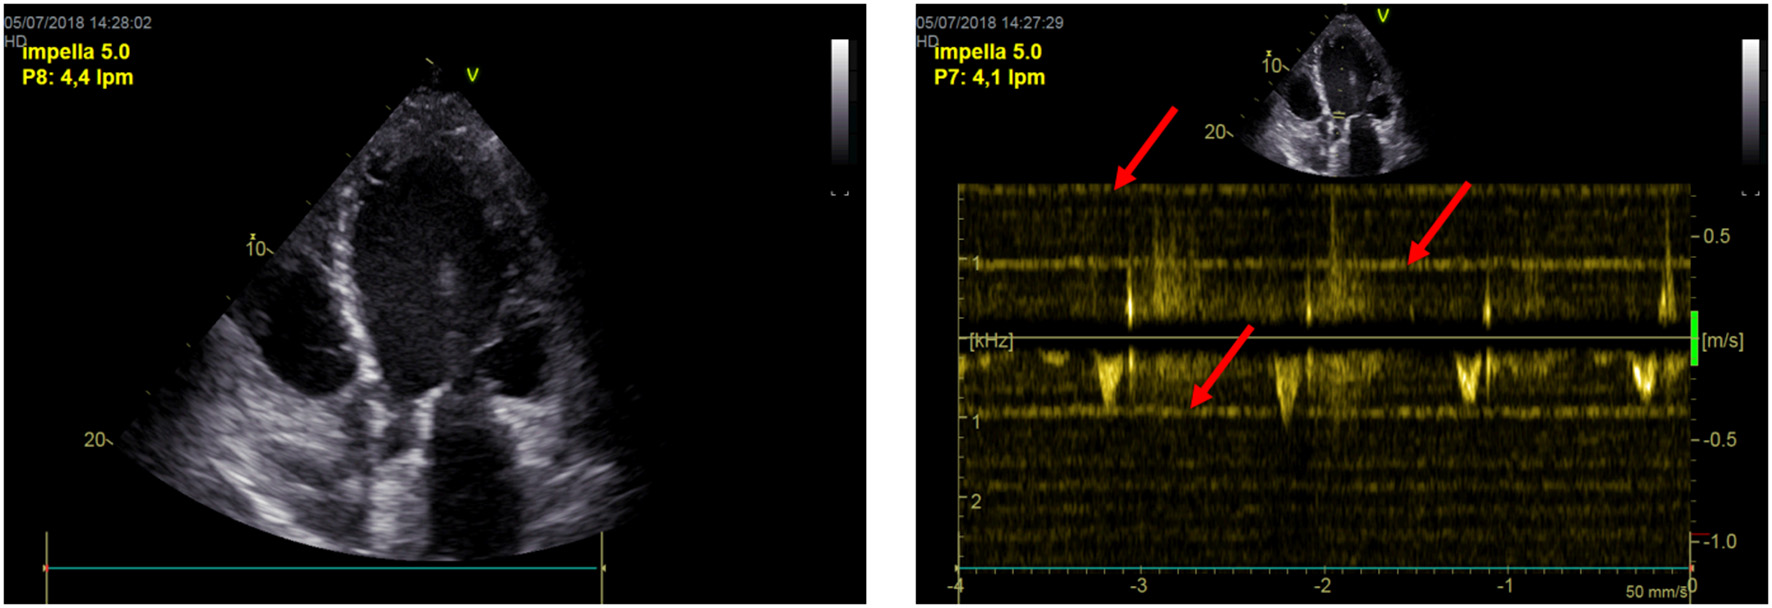

Baseline measurements are acquired during full Impella unloading as well as during minimal Impella support (P2). To assess LV function during exercise-like conditions, steady-state PV loops are additionally acquired during handgrip at minimal Impella support over 2 min. Figure 1A (and related.gif files as online supplement) shows original tracings of Impella patients during rate change (from full unloading P8 to minimal support P2 and back) with the typical shift of the loops on the xy plane. Figure 1B (and related.gif files as online supplement) shows two patients with different study outcomes: on the right a patient who profited from unloading, showing no or minimal increase of LV end-diastolic pressure (EDP) during handgrip; on the left a patient who had an abnormal pronounced increase of LV EDP during handgrip, as a sign of blunted contractile reserve. With regard to LV EDP, a novel Impella system has been introduced on the market, called smart assist (Figure 2). This system displays real-time LVEDP, mean arterial pressure (MAP), and cardiac power output (CPO) directly on the Impella console, and will probably play an important role in the future, especially with regard to the weaning process.

Figure 1

(A) LV pressure-volume loops (original tracings) from patients during Impella-rate reduction (P2, marked in yellow, on the left) as well as back to maximal unloading (P8, on the right). The typical shift on the xy plan is observed. (B) LV pressure-volume loops (original tracings) from patients during handgrip. On the right a patient who profited from unloading, showing no or minimal increase of LV end-diastolic pressure (EDP, red arrow) during handgrip; on the left a patient who had an abnormal pronounced increase of LV EDP during handgrip, as a sign of blunted contractile reserve.